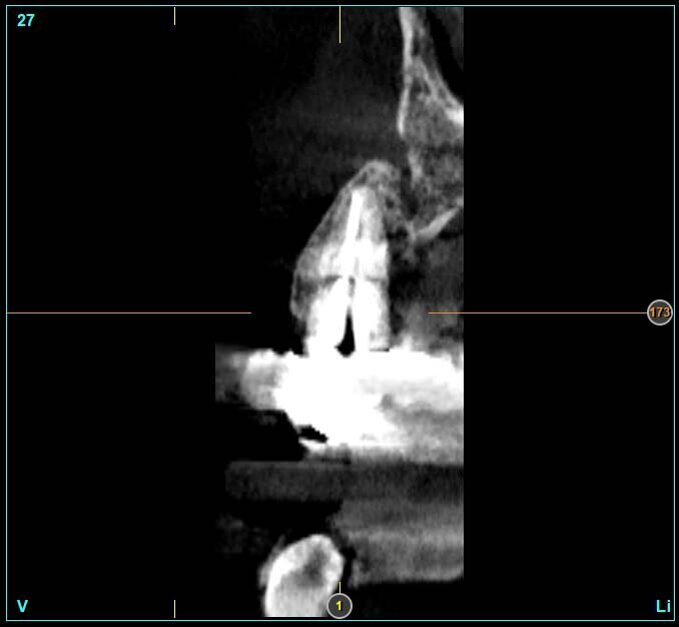

Il dente all’osservazione clinica e radiografica appare devitalizzato e ricostruito per mezzo di una perno moncone fuso e una corona in metallo ceramica collegata ad una corona sul dente 1.4 (Figg. 1, 2). All’esame parodontale si rileva un sondaggio puntiforme in zona palatale che indica la presenza di una frattura radicolare (Fig. 3). La paziente riporta una precedente apicectomia a carico del dente 1.2, come si evince dall’esame come-beam che ne evidenzia gli esiti a carico dell’osso apicale all’elemento 13 (Fig. 4).

Le corone sui denti 1.3 e 1.4 furono rimosse, il dente 1.3 fu estratto e l’alveolo fu riempito con una membrana di PRGF ottenuta tramite centrifugazione del sangue della paziente con il sistema Endoret e un provvisorio fu consegnato sui denti 1.3 e 1.4 (Fig. 5, 6). Dopo otto settimane fu eseguita una nuova cone-beam e la chirurgia fu pianificata (Fig. 7). Si eseguì un lembo a tutto spessore, fu eseguita l’osteotomia e fu inserito un impianto BTI Core 3.5 × 8.5. Un pilastro Unit fu avvitato e un tappo di guarigione fu applicato. L’osso ottenuto dalla fresatura mescolato con una membrana di PRGF fu applicato sul lato palatale per compensare una piccola deiscenza, una seconda membrana fu applicata sopra l’osso circostante e un innesto di tessuto connettivo prelevato dalla tuberosità fu suturato vestibolarmente per ricreare la bozza canina. Punti di sutura staccati furono eseguiti con un filo in PTFE (Figg. 8-11). Dopo quattro mesi il provvisorio fu rimosso e i tessuti apparivano sani e con un buon spessore di tessuto connettivo vestibolare per garantire la stabilità nel tempo del risultato. Fu eseguita un’impronta con la tecnica del cucchiaio aperto e dopo due settimane furono consegnate una corona in zirconio cementata sul dente 14 ed una avvitata sul denta 1.3. Il profilo di emergenza della corona sull’impianto appariva ideale. Purtroppo, a causa della mancanza del picco osseo sul versante distale del dente 1.2, non si ottenne una papilla di altezza adeguata. Ciononostante la paziente si disse soddisfatta del risultato e rifiutò ulteriori terapie per correggere il difetto residuo (Figg. 12-15).

La presenza di difetti ossei dopo l’apicectomia eseguita sul dente 1.2 fece decidere di non eseguire un impianto post-estrattivo immediato. La presenza dei difetti ossei e la presenza di cicatrici a carico dei tessuti molli rendeva di difficile esecuzione procedure di GBR che richiedessero il rilascio dei lembi. Si decise pertanto di compensare la perdita di tessuto vestibolare con un innesto di tessuto connettivo. L’inserimento di un impianto di 8,5 mm permise di ottenere un asse di inserzione ideale e di avere il foro di fuoriuscita della vite collocato palatalmente senza il bisogno di correggere l’angolazione. Tutto ci. ha permesso di eseguire procedure chirurgiche e protesiche semplici e ben sopportate dalla paziente e soprattutto di raggiungere un buon risultato estetico e funzionale.